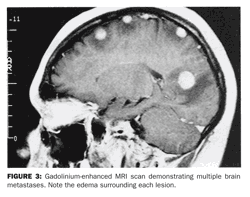

Radiographic appearance of metastatic lesions On CT or MRI, most brain metastases are enhancing lesions surrounded by edema, which extends into the white matter (Figure 3). Unlike primary brain tumors, metastatic lesions rarely involve the corpus callosum or cross the midline.

The radiographic appearance of brain metastases is nonspecific and may mimic other processes, such as infection. Therefore, the CT or MRI scan must always be interpreted within the context of the clinical picture of the individual patient, particularly as cancer patients are vulnerable to opportunistic CNS infections or may develop second primaries, which can include primary brain tumors.